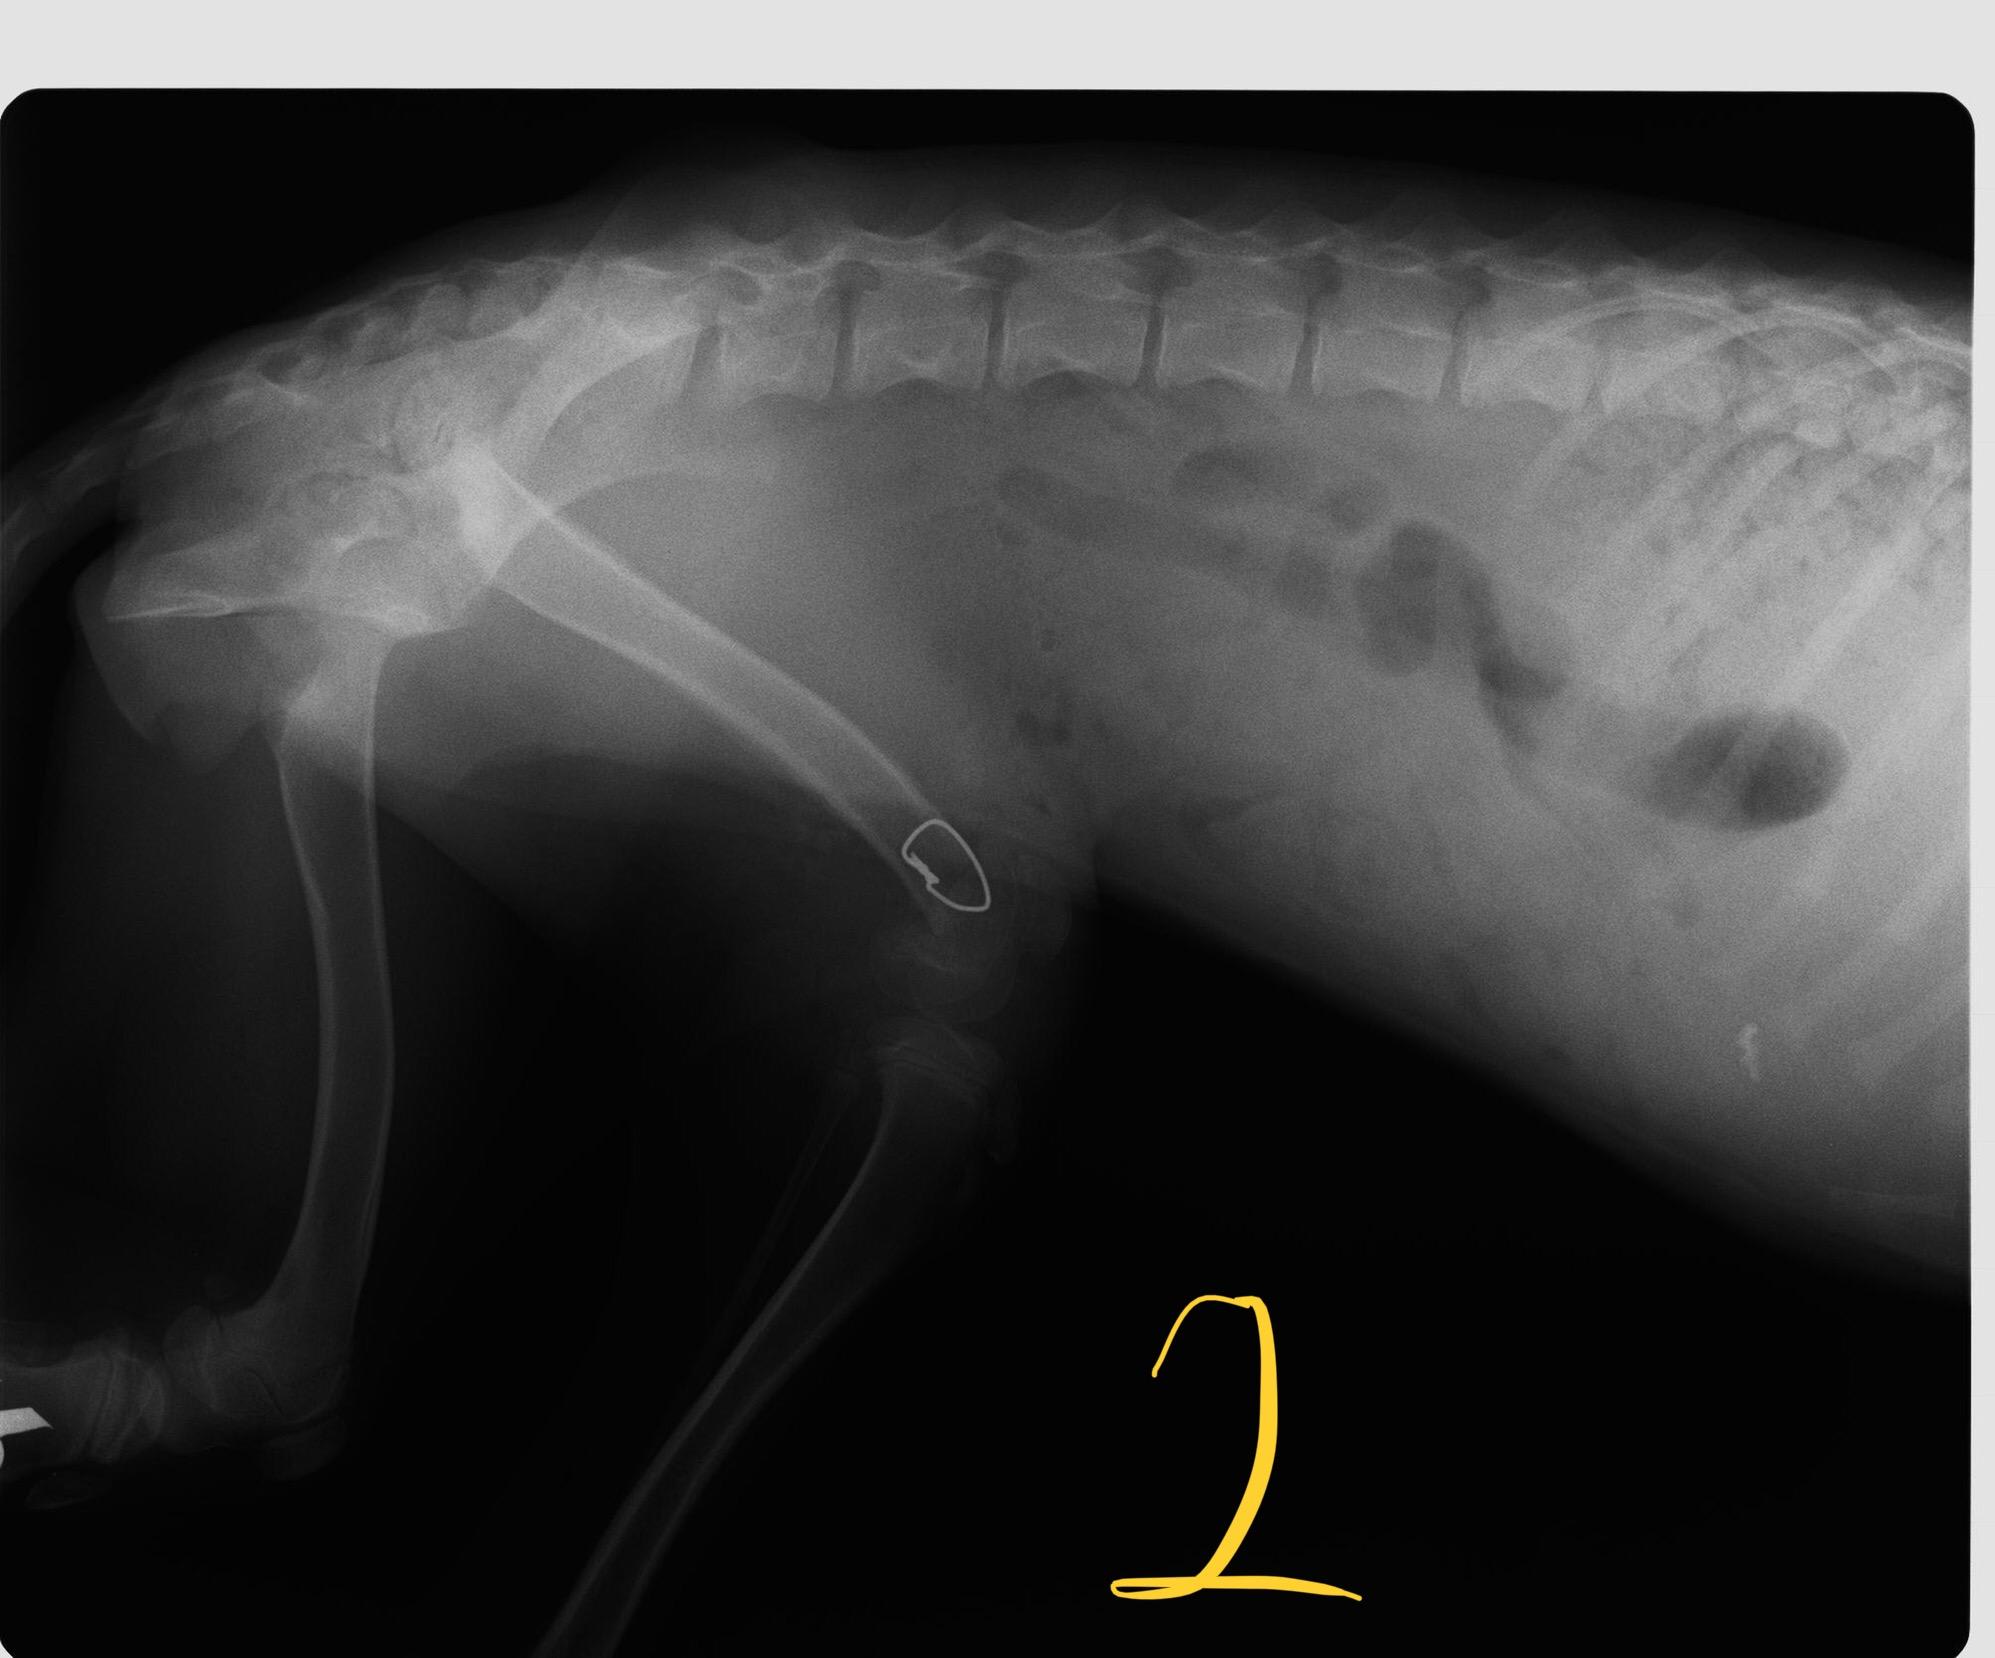

HEALTHSHARE My vet said Ella needs her back left leg amputated since the 1st operation she had was not successful. She can walk and run with a slight limp. She had the operation when she was a puppy 4/5 mi this old. Now she is 11 months old. Photo 1 pre op. Photo 2 after op. What do you think. Kind regards Pet's info: Dog | Mixed Breed Medium (23 - 60lb) | Female | spayed | 11 months and 22 days old | 38 lbs Location: United Kingdom

Thank you for reposting your question with pictures. The second x-ray is a little dark and is difficult to read, but I can certainly see that the area is not normal and why your vet would recommend amputation since the area will not get any better. However, if Ella only has a slightly limp, then I'm not sure why the amputation needs to happen now. Some dogs do very well with an abnormal leg for many years. If at some point it starts causing her more problems, it can always be amputated at that time. And certainly only having 3 legs puts more strain on the other legs, so we try to wait to amputate unless the leg is currently painful or causing problems. Good luck! I hope that was helpful and answered your question. Thanks for using Petco Pet Education Center, formerly Petcoach.